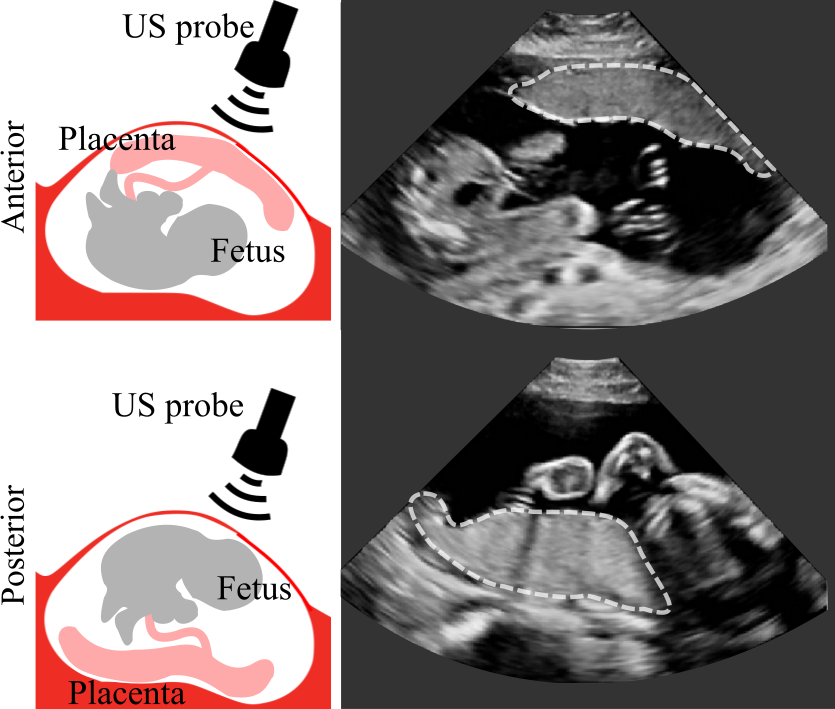

First, we consider variability in appearance. A major factor affecting placenta appearance in US is the location of the placenta. Anterior placentas are located at the front of the uterus towards the mother’s abdomen, and posterior placentas at the back of the uterus towards the mother’s spine, bottom) (see Fig. 1). Anterior placentas are closer to the US probe, yielding higher contrast between placental and other tissues. On the other hand, the appearance of posterior placentas in US often suffers from shadows (the fetus can lie between the US probe and placenta) and attenuation artifacts. The placenta can be located in any position between the anterior or posterior of the uterine wall with the most common positions being anterior, posterior, lateral and fundal (placentas located at the left or right lateral and top of the uterus, respectively).

In particular, we propose a multi-task approach combining the classification of placental location and semantic placenta segmentation in a single artificial neural network. The location classification as pretext task informs the network about the data variability to improve performance in unfavorable training set conditions for segmentation, which is the clinical downstream task. We discretize the placenta location in three classes: anterior, posterior and none. Anterior includes placentas located towards the front uterine wall between the fetus and the US probe, and posterior includes placentas located towards the back uterine wall with the fetus and amniotic fluid between the placenta and the tip of the US probe (see Fig. 1 (a)). None comprises images without placental tissue, independent of the global image label from the corresponding patient.